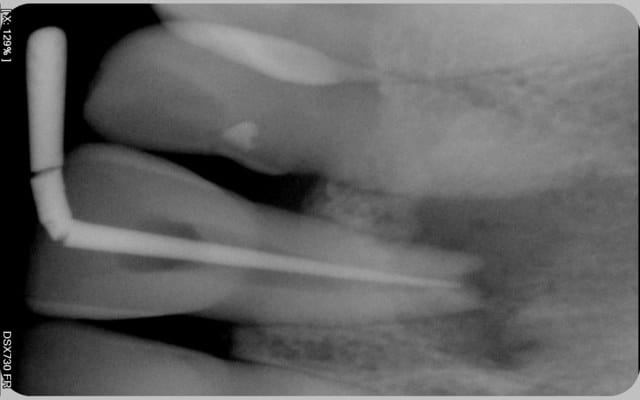

Voici les photos.

Comme vous pouvez le voir la lésion est très importante. Pensez-vous que cette dent ai une chance? Mon maître de stage lui laissait 40% de chance, je n'ai pas de recul mais ça me semble beaucoup. J'ai preferé dire au patient que ça serrait délicat car il n'imaginait même pas la possibilité d'enlever la dent.

Pour la résection apicale, j'y avais penser mais la racine me semble déjà bien courte.

Avant xzcl7i - Eugenol

C ne en place ug4pvg - Eugenol

Obturation ocz3kw - Eugenol

excusez moi pour l'orientation des radiographies

je précise qu'en vestibulaire, il y a une voussure, c'est dépressible ce qui me premet de penser à la perte de la table osseuse externe